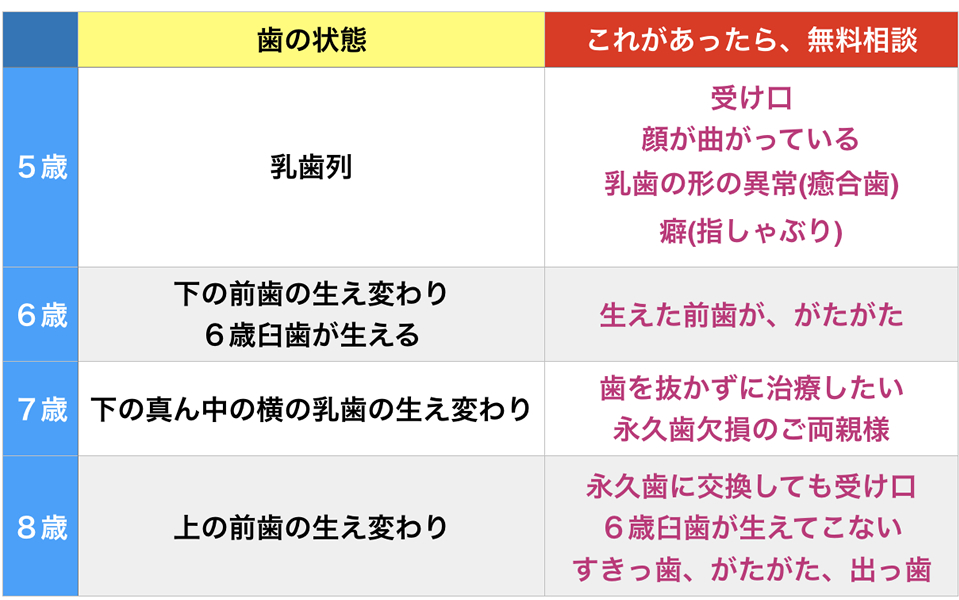

第 Ⅰ 期治療 6歳までが乳歯列期、6歳になると下の前歯が生え替わり始め混合歯列期に入ります。また、6歳臼歯と言われる、第1大臼歯が生え始めます。6歳~8歳で上と下の前歯が生え揃います。この時期までには、第 Ⅰ 期治療は開始されると良いと思います。 8歳~10歳までは、乳歯から永久歯の交換は行われず、この時期に矯正治療は、行いやすいです。10歳~12歳では、横の乳歯が永久歯への交換時期になります。一般的には、同じ部位なら、下の歯の方が早く生え替わり始めます。また、左右、同時期に生え変わった方が、不正咬合は引き起こしにくいです。 |

第 Ⅱ 期治療 12歳で、第二大臼歯が生え始め、永久歯列の完成となります。 この時期からの矯正治療を第 Ⅱ 期治療と言います。 親知らずは、18歳~30歳で生え始めます。親知らず萌出時には、第二大臼歯を押しながら、萌出してくることが多く、早期に抜歯することも検討する必要があります。 |

子供の矯正開始時期は7~9歳 です。成長を利用した矯正を行えます。

0歳ぐらいまでは、顎の成長が旺盛であり、その成長を利用した治療が可能だからです。12歳を超えると、矯正治療による治療は、主に歯の移動によるものになってしまいます。当院では、手のレントゲンを撮影分析することにより、患者様各々の成長時期を考えた治療を行っていきます。年齢と歯の交換時期と成長の時期は、異なります。

お母様から、子供の矯正治療はいつ頃から始めたらよいのかわからないという質問を受けます。

子供の矯正治療を始める時期は、そのお子様によって適切な開始時期は異なります。

反対咬合の場合、3歳児検診で指摘されることが多いです。

下の歯が上の歯より前に出ている受け口(反対咬合)は今まで3歳児検診で指摘されても、「永久歯になれば改善されることもありますので、しばらく様子をみましょう。」ということがよくありましたが、データによると3歳で受け口の場合、自然に治るのは6%(100人に6人)くらいしかいないそうです。